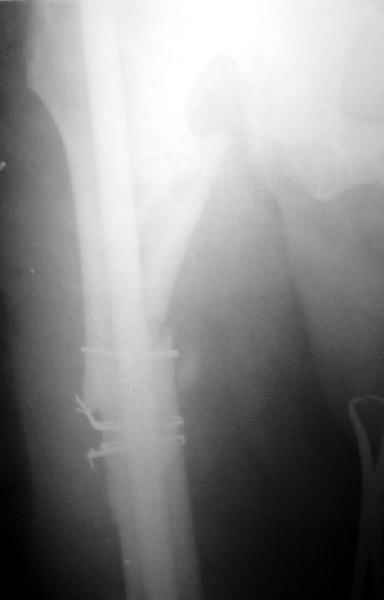

Еще один пример - несращение через полгода после несостоятельного остеосинтеза, и через полгода после реостеосинтеза с блокированием.

1

2